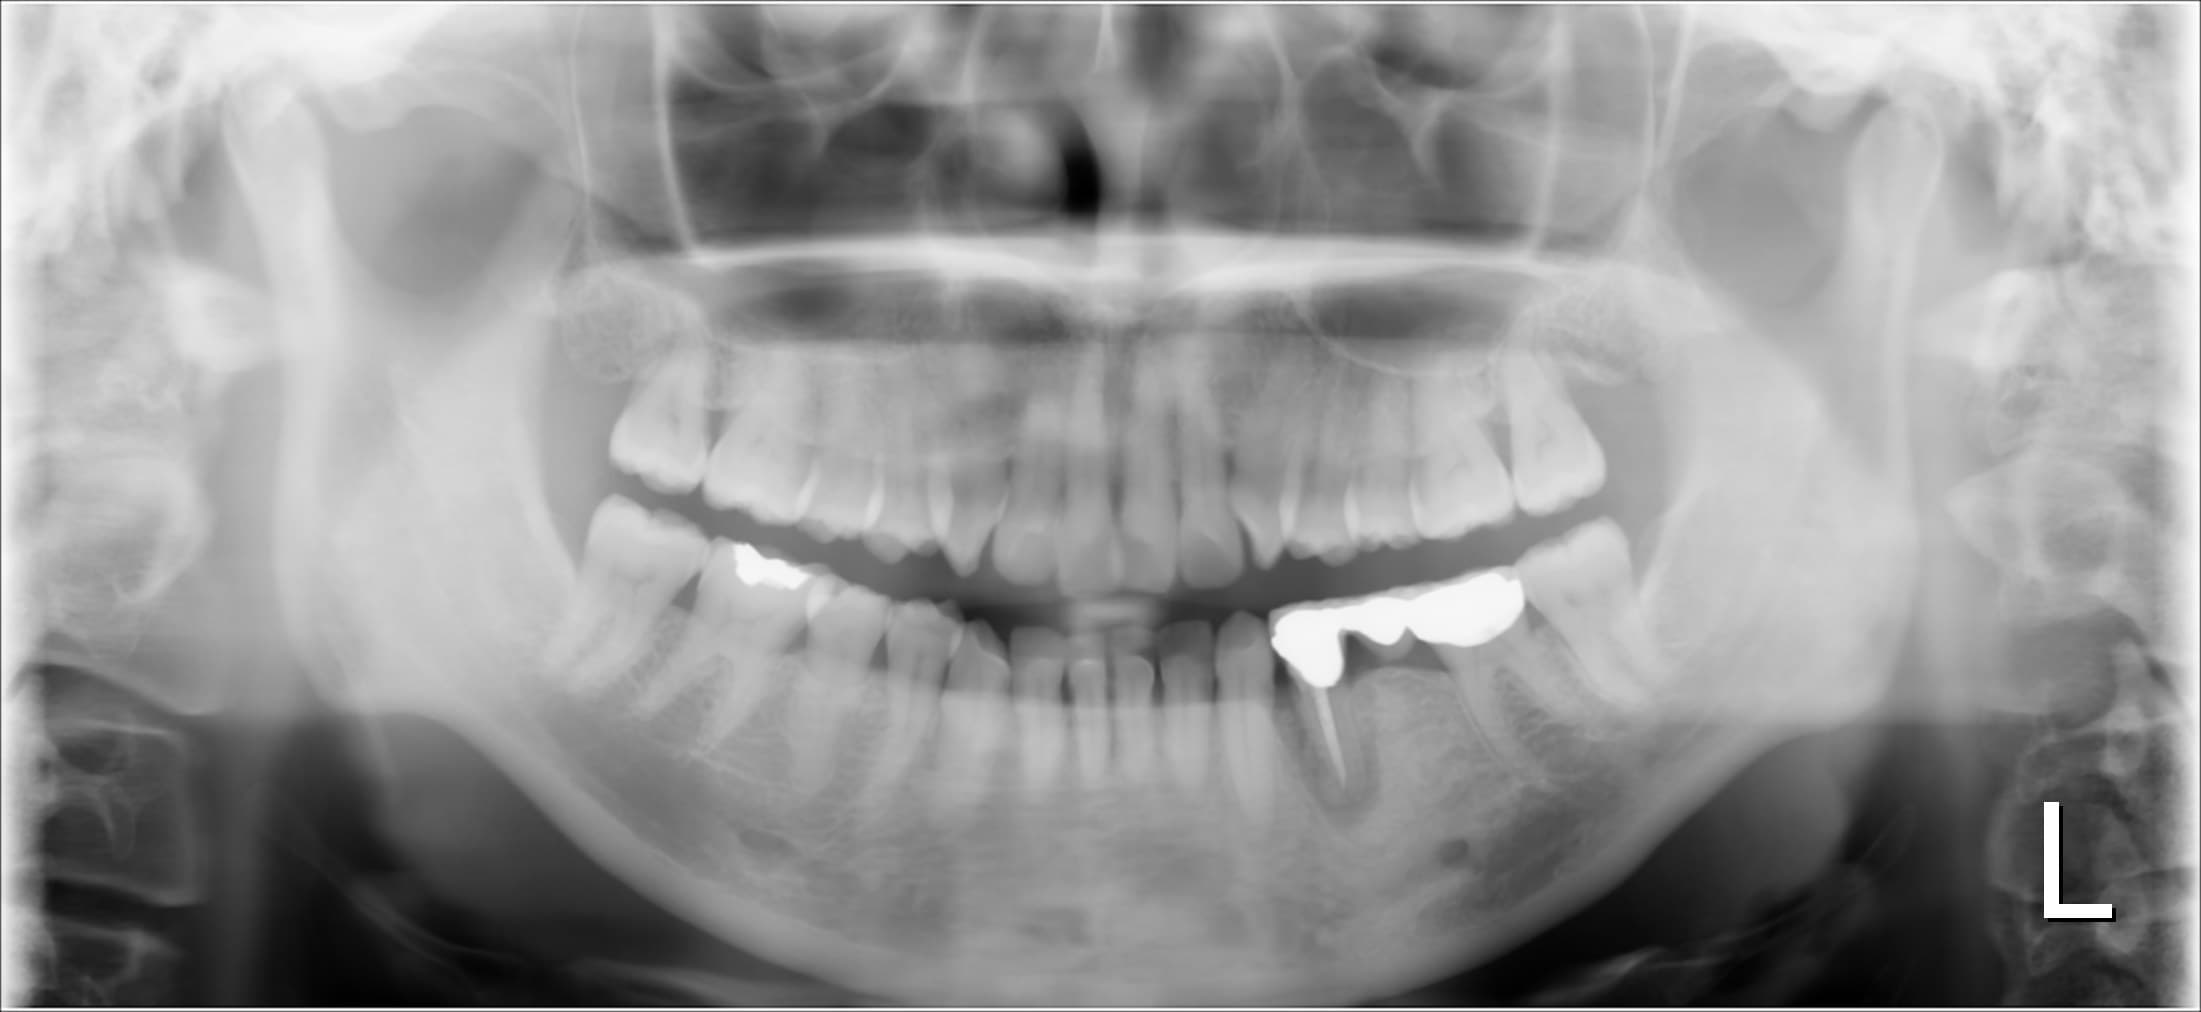

今回ご紹介する歯周専門治療のケースは、40代女性の方です。

以前より左下の歯に痛みを感じており、他院を受診した際、経過観察を提案されましたが、痛みが強くなった為、当院へ相談にいらっしゃいました。

レントゲンで確認すると、骨が大きく欠損しており、また口腔内では、はっきりと歯にひびが入っていることも確認できた為、ご相談の結果、インプラントを前提として抜歯を行うこととなりました。

そして、インプラントを長期安定させる為にも、現在よりも徹底した歯周病の管理が必要なことをお伝えし歯周専門治療を行っています。